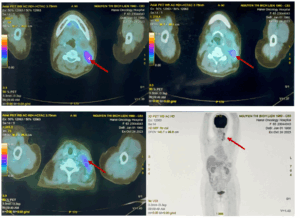

CASE LÂM SÀNG: CHẨN ĐOÁN BỆNH NHÂN ĐỒNG MẮC BA LOẠI UNG THƯ TẠI TRUNG TÂM Y HỌC HẠT NHÂN VÀ UNG BƯỚU, BỆNH VIỆN BẠCH MAI

CASE LÂM SÀNG: CHẨN ĐOÁN BỆNH NHÂN ĐỒNG MẮC BA LOẠI UNG THƯ TẠI TRUNG TÂM Y HỌC HẠT NHÂN VÀ UNG BƯỚU, BỆNH VIỆN BẠCH MAI GS. TS. Mai Trọng Khoa, PGS. TS. Phạm Cẩm Phương, PGS. TS. Phạm Văn Thái, BSNT. Đỗ Thị Thu Trang Trung tâm Y...